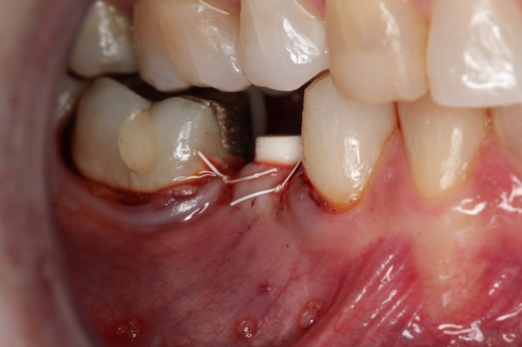

Fig 12. Ceramic implants placed and sutured.

Figure 12

Figure 10 through Figure 13 show the preoperative x-ray and the sequence of beginning with healed sites through the surgical placement of the implants. The implants were protected by an Essix-style wound-protection removable retainer for approximately 12 weeks. After the integration phase, the implants and the natural dentition were prepared using traditional crown-and-bridge high-speed diamond and zirconia cutting burs to remove decay and existing restorative materials, to complete and refine the natural-tooth structures to receive full-crown coverage, and to prepare and refine gingival margins of the zirconia implants where needed.

Occasionally dentists are presented with extreme challenges with long-term restorations and replacing missing teeth. Dentists must evaluate the patient's condition, develop optimum long-term oral health, and attempt to meet the patient's expectations. Figure 18 showed a class III malocclusion with deep bite, multiple abfractions, and less-than-ideal occlusal plane, but the patient wanted to replace his maxillary right canine only. A discussion with the patient regarding occlusal disharmonies and comprehensive recommendations for full-mouth rehabilitation revealed that the patient had a limited budget for dental care. The patient understood the ramifications of his comprehensive dental needs not being affordable. Decisions were made to atraumatically remove the maxillary right canine (Figure 19) and immediately place a ceramic dental implant (Figure 20). Polytetrafluoroethylene (PTFE) 4-0 sutures were placed to help support soft tissues, and then a full-arch Essix-style retainer with a flowable composite facial veneer was used to provide some esthetics during the patient's healing phase (Figure 21). The implant and the retainer were not to be in contactthe retainer may occlude with the opposing dentition and also be passive in relation to the ceramic implant.

Sutures were removed 2 weeks after surgical implant placement, and the patient was instructed to continuously wear his Essix-style retainer for 12 weeks. The retainer was worn while eating during the 12-week period. The patient returned at 12 weeks for soft-tissue and implant-bone evaluation (Figure 22). At this appointment, minimal lingual soft-tissue manipulation was performed by gingival abrasion to the keratinized soft tissue and an aluminum chloride gel was placed.